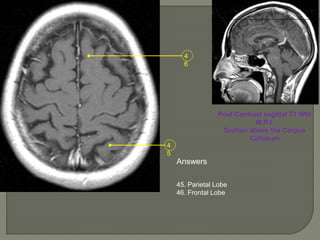

Post Contrast sagittal T1 Wtd

M.R.I.

Section above the Corpus

Callosum

Answers

45. Parietal Lobe

46. Frontal Lobe